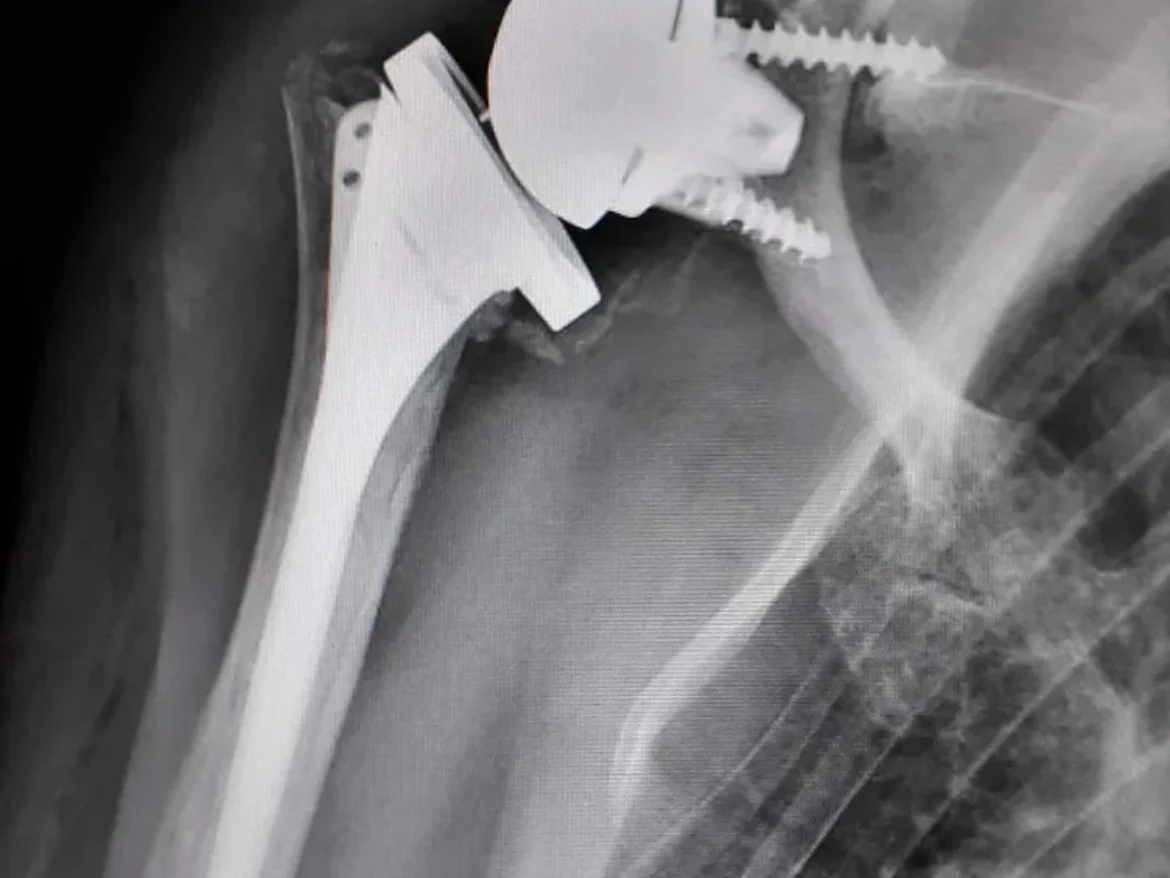

PROTHÈSE DE L’ÉPAULE

En savoir plus